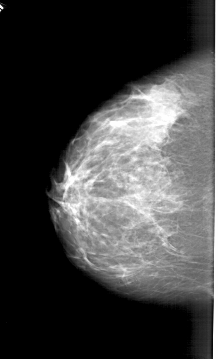

A_1394_1.RIGHT_MLO

RIGHT_MLO LINES 6046 PIXELS_PER_LINE 3526 BITS_PER_PIXEL 12 RESOLUTION 43.5 OVERLAY